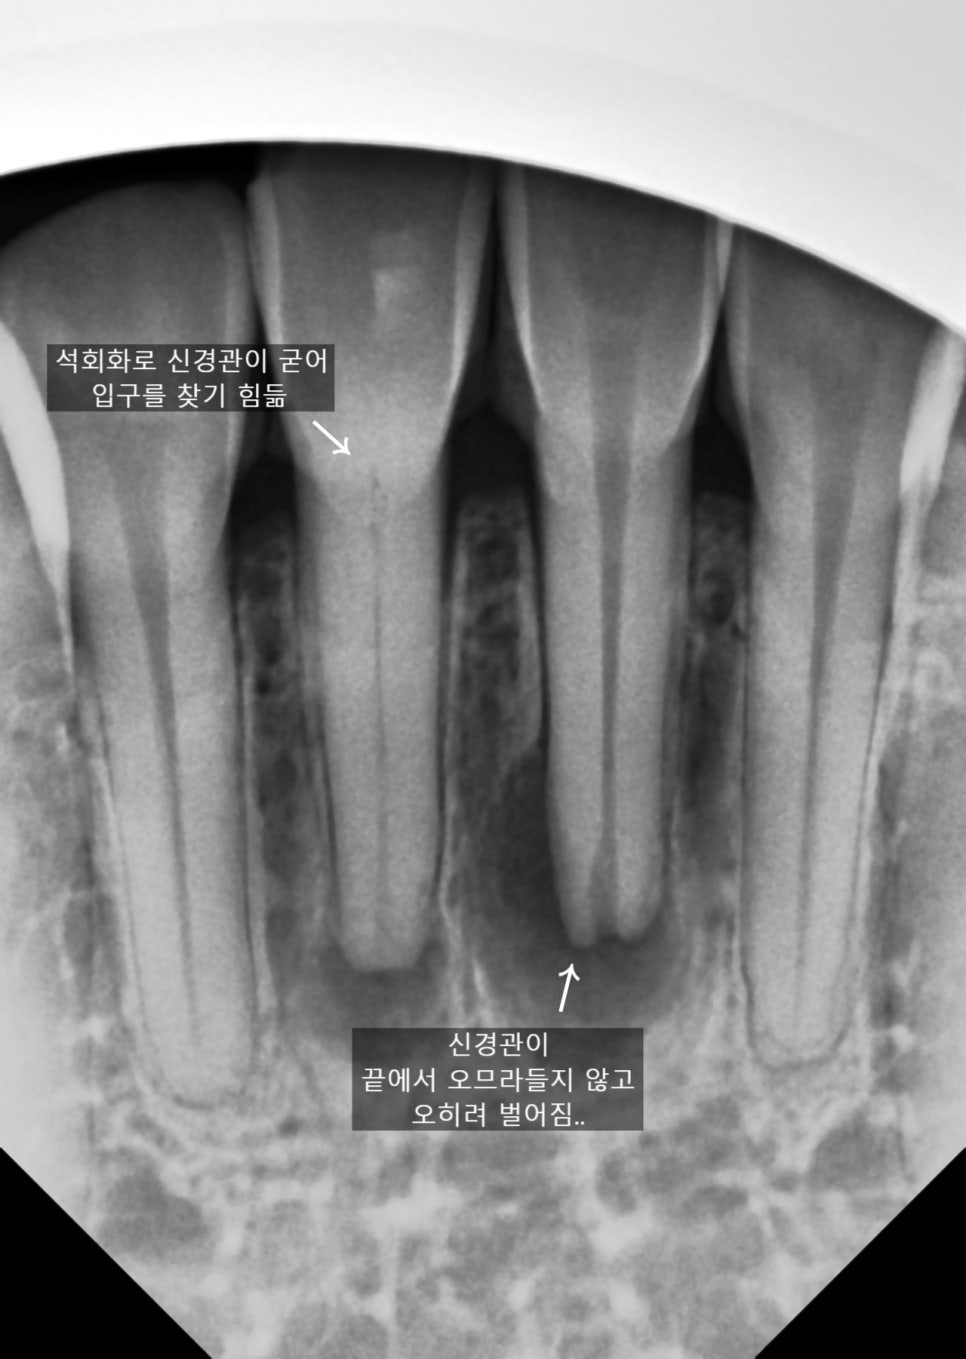

신경치료를 어렵게 만드는 요인

석회화로 신경관을 찾기 힘든 경우

길을 제대로 들어가지 않으면

치아에 엉뚱한 구멍을 내거나

치아를 약하게 만들 수도 있는 등

치료가 굉장히 어렵습니다.

또, 신경관이 끝에서 벌어지면

그 벌어진 사이즈를 기준으로

윗부분도 많이 수작업을 해야해서

굉장히 어렵죠.